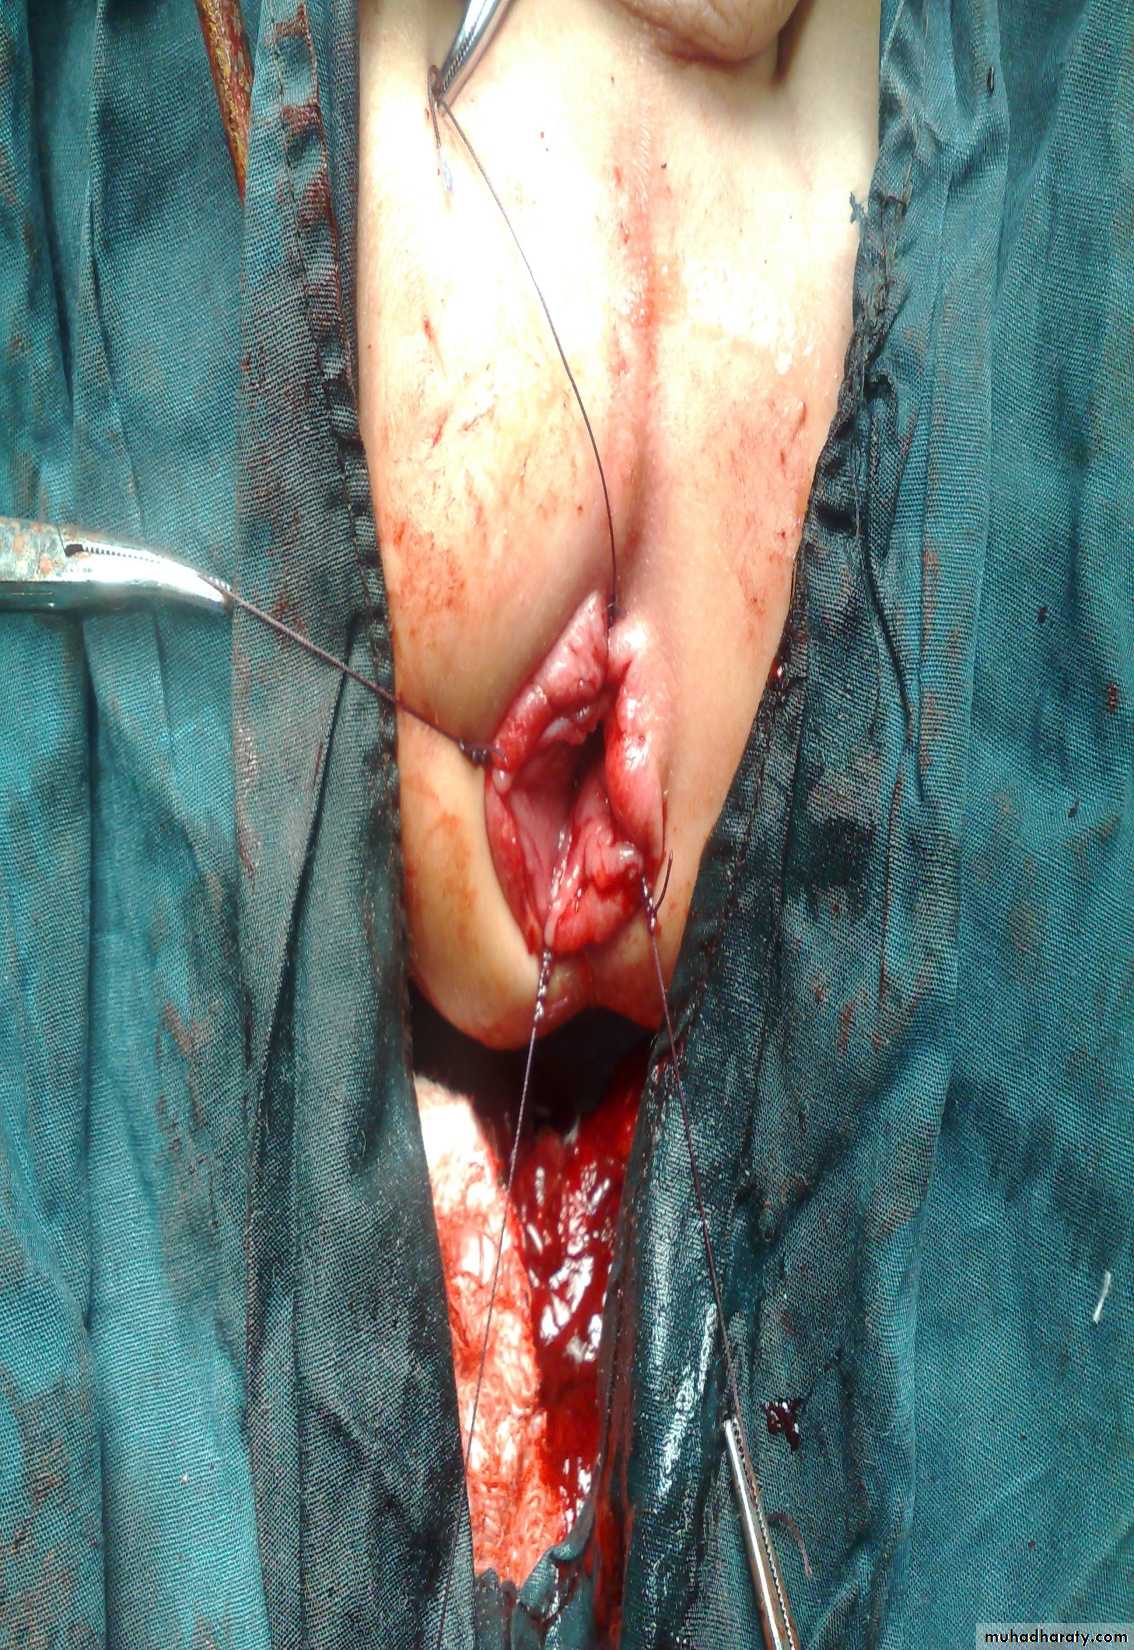

Surgery called pull-throughAbdominal Wall Defects

Diagnosis: omphalocele

Description:• Huge dilatation

• Central umbilicus

• Liver present

Treatment:

It is no emergency condition• Cover

• Incubation

• Give fluid

• Use silo bag

First photo:

Diagnosis: gastroschisisDescription:

• No sac

• Right to the umbilicus

• Associated anomalies are less

It is emergency condition• Reduction

• Close the defect